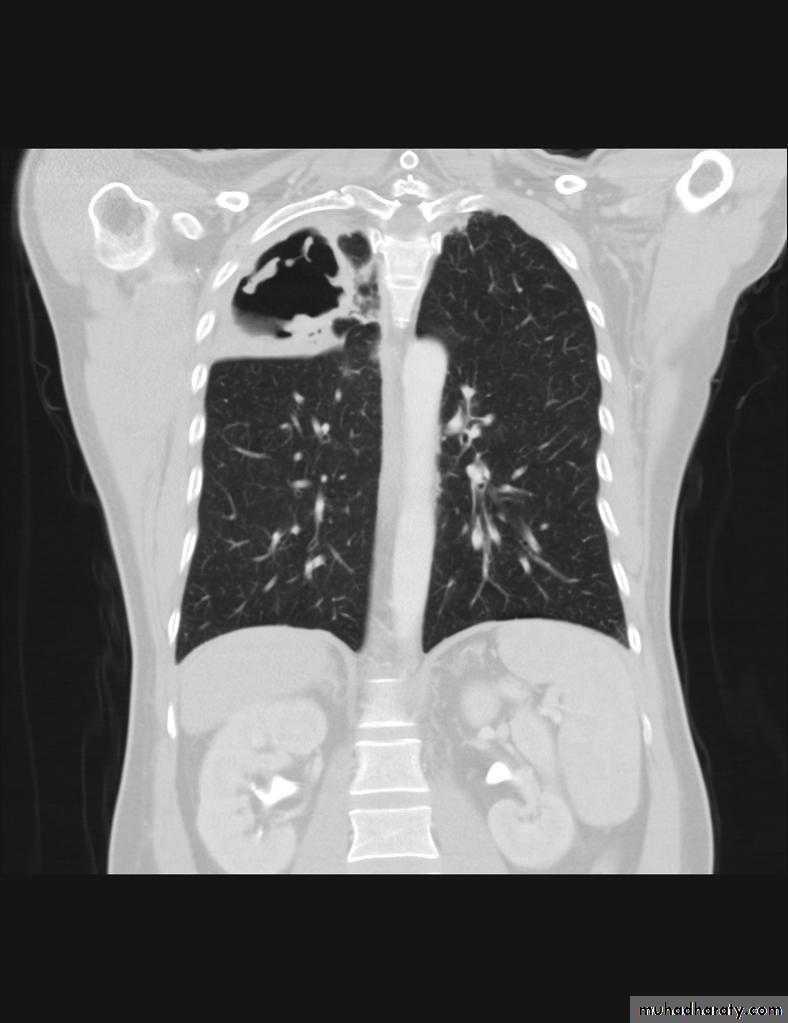

Miliary TBBilateral diffuse tiney nodules1-3 mm in diameter uniform in size and uniformly distributed involve whole lung fields.

miliary TB